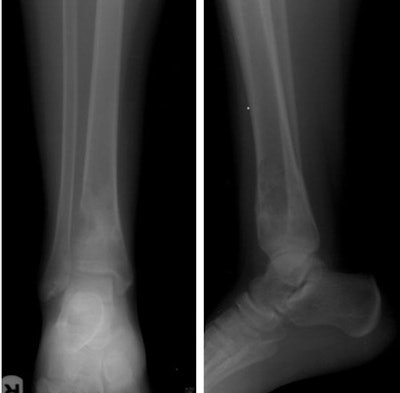

In all, 49 patients including 23 men and 15 women (mean age 33.7 years, range 4-77 years) underwent image-guided biopsies. Imaging in the cohort included radiography, CT, and MRI, and the study team categorized the records according to the location of the host bone, presence or absence of an extraosseous soft-tissue component (usually at MRI), and imaging nature of the lesion matrix (usually at CT) including lytic, sclerotic, or mixed lytic and sclerotic.

Cross-sectional imaging showed an extraosseous component in about half (26/49) patients, which facilitated biopsy and obviated the need for cortical breach, the authors wrote. The other 23 patients had completely intraosseous lesions that required more aggressive efforts to reach the lesion, the study team wrote.

Based on imaging findings at CT and x-ray, initial diagnostic yield was higher for mixed lesions (94%), followed by sclerotic (89%) and lytic (83%) lesions, according to the authors. As for the completely intraosseous lesions, the diagnostic yield was 74%, while the presence of extraosseous soft-tissue components raised the diagnostic yield to 100% in 26 cases.

The lesion matrix, as visualized on the different imaging modalities, is a major factor determining the biopsy instrumentation choice and percutaneous biopsy decision, the authors wrote. In line with previous studies, the study reached higher diagnostic yields for lesions of mixed matrices, followed by sclerotic lesions and lytic lesions.